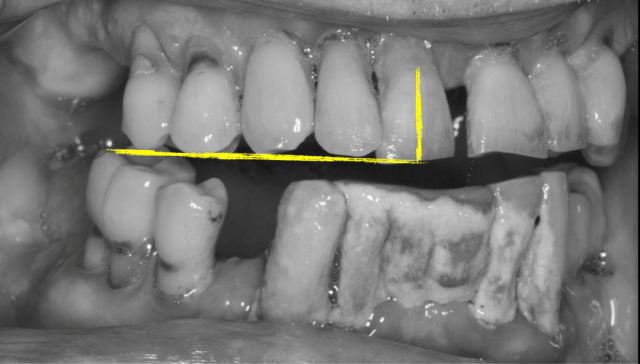

Many patients with advanced periodontal disease have responded well to treatment and maintenance over time. This patient presented with visibly mobile teeth and elected to proceed with a restorative dental treatment plan that included the removal of all remaining teeth. When the teeth are mobile, can the tooth position on the master model be accurate for use as a reference point when placing denture teeth? The other question is, when the teeth are mobile, how many chances do I have to make the impression?

The identification and transfer of landmarks in the final impression are critical in the evaluation of tooth position on the working model. Specifically, it’s hard to know if the teeth moved facially or palatally during the impression process.

2. Make an initial impression, with the goal being to record the palatal vault area and to index the occlusal/incisal aspect of the natural teeth to serve as a reference point when reinserting the impression.